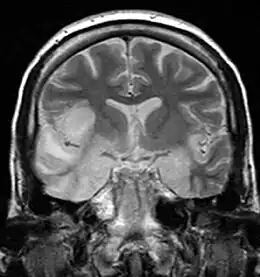

Image IRM d'une encéphalite herpétique montrant des anomalies au niveau du lobe temporal.

L'IRM cérébrale est anormale dans 90 % des cas[6]. Elle montre des images unilatérales (ou asymétriques) au niveau des lobes temporaux ou frontaux. Elles ne sont pas spécifiques et peuvent être retrouvées dans d'autres encéphalites, infectieuses ou non.